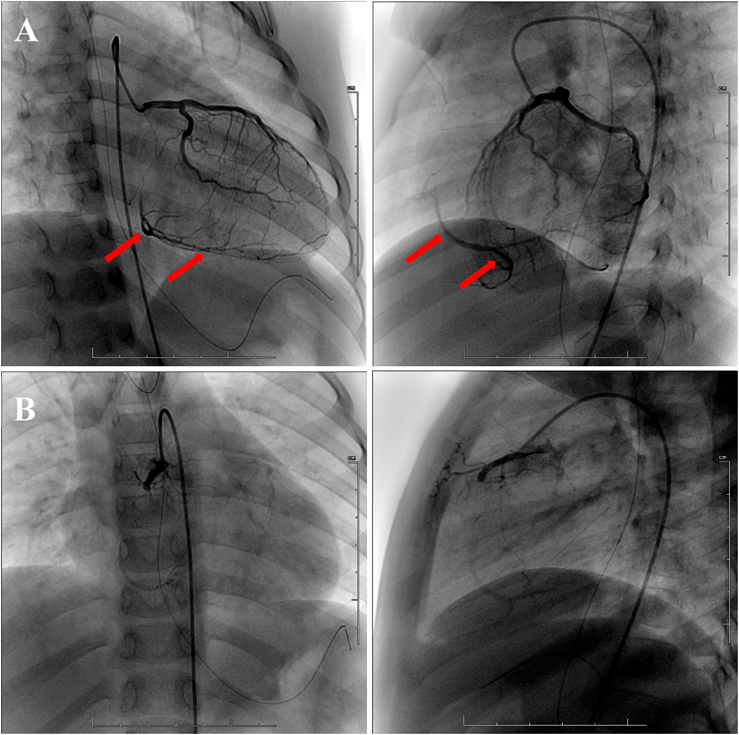

At three months after admission, left coronary angiography (CAG) showed no dilatation or stenosis through the left coronary artery (LCA) and supply to the RCA distal segment via a well-developed collateral circulation from the LCA (Fig. 5A). Right CAG revealed complete occlusion of the RCA with formation of a slight collateral circulation from the proximal RCA (Fig. 5B). The patient has been maintained with ACE inhibitors, β-blockers, warfarin, and aspirin, and has continued to undergo regular echocardiography and ECG as an outpatient. LVEF has improved to ≥60%. The abnormal Q wave of III and aVF remain on ECG, but ST of the chest leads has normalized.

Journal of Pediatric Cardiology and Cardiac Surgery 6(1): 25-30 (2022)

Fig. 5 (A) Left CAG showed that the LCA had no dilatation and no stenosis, and that the RCA distal segment was supplied by a well-developed collateral circulation from the LCA (arrow). (B) Right CAG revealed complete occlusion of the RCA with formation of a slight collateral circulation from the proximal RCA

CAG, coronary angiography; LCA, left coronary artery; RCA, right coronary artery.